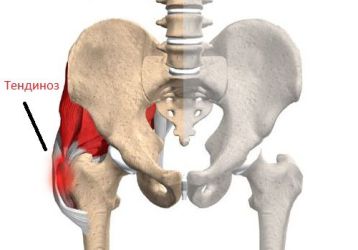

Что такое тендиноз тазобедренного сустава и как его лечить?

Что такое тендиноз тазобедренного сустава: лечение при помощи физиотерапевтических процедур. Список медикаментов и описание хирургии.